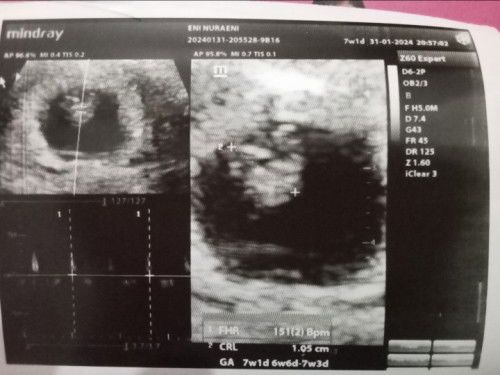

USG 7W ..

Bun tadi saya usg , usia kehamilan saya 7W , Alhamdulillah uddah ada djj nya kata dr bayiku sehat , tapi tadi aku di resepin obat penguat kandungan karena lendir keputihanku ada darahnya , aku khawatir banget bun , terus itu baby nya emang gitu ya posisi normalnyaa bun ??